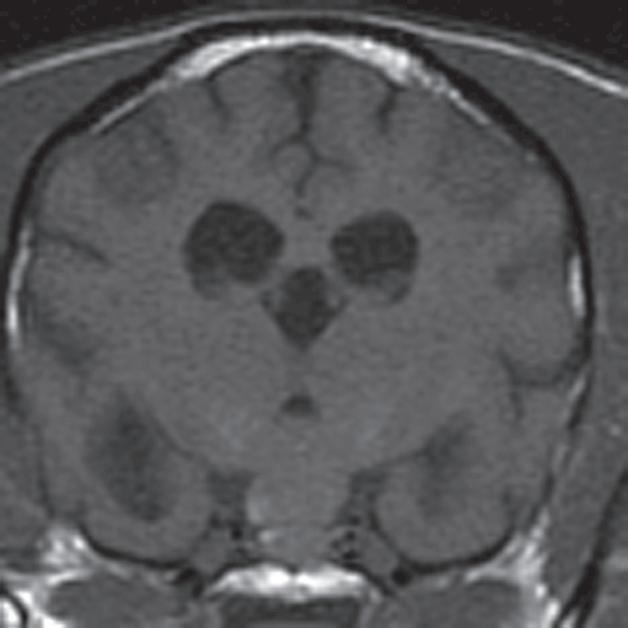

Badanie wykonano u 14-letniej, kastrowanej samicy szpica z przechyleniem głowy i występującym od niedawna chodzeniem w kółko w prawą stronę. Ryciny a–c to reprezentatywne obrazy w płaszczyźnie poprzecznej na poziomie dołu przysadki. Ryciny d–f to analogiczne obrazy w płaszczyźnie strzałkowej. Przysadka mózgowa była znacznie powiększona (wysokość = 10 mm, szerokość = 10 mm), izointensywna w obrazach T1-zależnych (a, d) i łagodnie hiperintensywna w obrazach T2-zależnych (b, e) w porównaniu z istotą szarą głęboką. Stwierdzono również poszerzenie układu komorowego (wentrikulomegalię), które może wynikać z częściowej niedrożności. Przysadka uległa jednorodnemu wzmocnieniu kontrastowemu (c, f), a w badaniu pośmiertnym wykazano, że miała postać dobrze odgraniczonej, kulistej masy (g). Potwierdzono, że zmiana była makrogruczolakiem przysadki